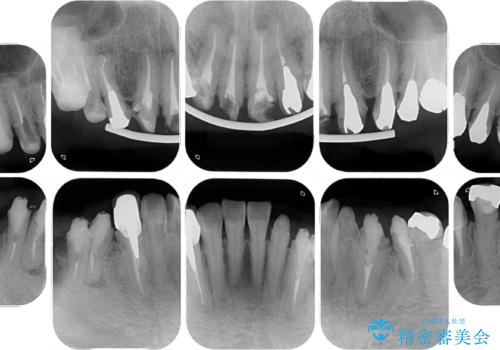

- 近医にて古いかぶせ物をセラミッククラウンにしようと治療を開始したものの、仮歯での咬み合わせが不安定とのことで、転院を希望して来院された患者様です。

骨格的に下顎骨が前方位に位置しており、上下前歯部の先端同士が接触する切端咬合でした。

このような方は咬み合わせが大きく変わると不安定となるため、まずは装着されている仮歯で咬合調整を行い、安定した咬み合わせとした後に、新しい仮歯に置き換え、その後オールセラミッククラウンにて補綴治療を行うこととしました。